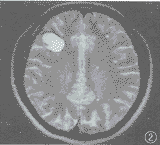

胸片示右肺门增大,上野见斑片状模糊阴影。CT扫描见:右肺上叶不规则斑片状病灶,有毛刺及纤维条索(图1)。小脑上蚓部见一边界清楚的低密度灶,无水肿区,右额顶叶见一大片状低密度区,其内见弧带状出血灶,右侧脑室略受压变形,右枕叶和左额叶各见一小圆形低密度灶。1个月后再次CT检查:颅内病灶仍存在,病灶囊变,右额顶叶病灶内出血影消失,病灶增强后不强化。5个月后胸片检查,右肺病灶消失;颅脑磁共振检查示原囊性灶仍存在,皮质下区及脑深部见多个小病灶(图2)。8个月时CT平扫:不见囊性灶,脑实质内见多发大小不一略高密度结节性病灶,占位不明显,以小脑半球居多(图3)。

图2 颅脑磁共振扫描,示原囊性灶仍存在,皮质下区及脑深部见多个小病灶